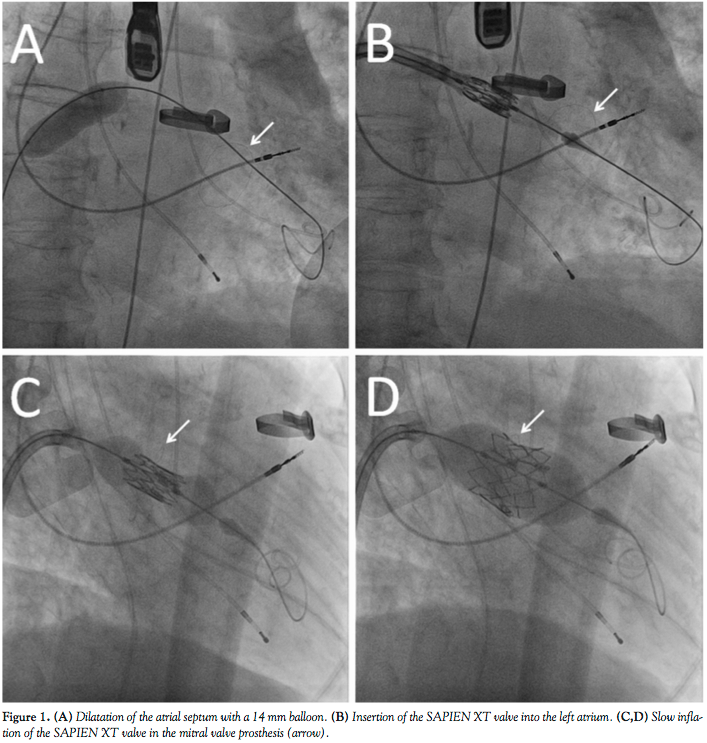

The patient was an 81-year-old woman with severe regurgitation of her 27 mm Epic mitral valve prosthesis (St. Jude Medical) and suffering from dyspnea on mild exertion (New York Heart Association [NYHA] III). The patient had received an open commissurotomy of the mitral valve for mitral valve stenosis 27 years ago and a mitral valve replacement 7 years ago for mitral valve endocarditis. Concomitant diseases include pulmonary hypertension, renal failure, and severely reduced lung capacity. Her calculated logistic EuroScore was 48% and her Society of Thoracic Surgeons (STS) score was 29%. Thus, another mitral valve replacement was refused by the patient and was considered as extremely high risk by the cardiac surgeon. After careful consideration and discussion with the patient and the cardiac surgeon, a transfemoral valve-in-valve implantation was planned, with informed written consent of the patient. The procedure was performed under general anesthesia. The femoral vein was used as an access site, followed by a transseptal puncture and placement of a super-stiff wire into the left ventricle. Then, the septum was dilated with a 10 mm and 14 mm balloon (Figure 1A) and an 18 Fr expandable sheath was inserted into the femoral vein. A 26 mm Edwards SAPIEN XT prosthesis was reversely mounted on a NovaFlex+ delivery catheter, and the valve alignment was performed in the caval vein (after a previous bench test to evaluate whether inverse valve alignment was feasible). The valve was inserted through the septum (Figure 1B) and then inserted into the mitral valve prosthesis. Under rapid pacing, a very slow inflation of the balloon was performed to ensure optimal placement (Figures 1C and 1D). After removal of the system, the Edwards valve was stable and showed no regurgitation. This was also confirmed after 1 week during a follow-up transesophageal echocardiogram (Figure 2). No residual shunt at the atrial septum was detected. The patient was transferred to a normal ward after 2 days with significantly reduced heart failure symptoms (NYHA I-II).